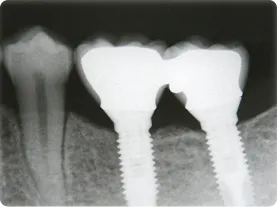

左下67 欠損に対してインプラント治療を行った症例

部分床義歯を使用していたが、どうしても慣れない上にしっかり噛むことができないためインプラント治療を希望